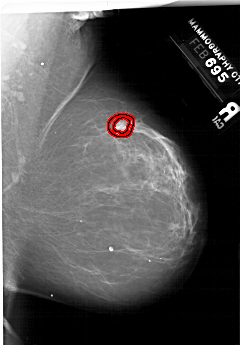

A_1999_1.LEFT_CC

RIGHT_CC LINES 6871 PIXELS_PER_LINE 4336 BITS_PER_PIXEL 12 RESOLUTION 43.5 OVERLAY

FILE: A_1999_1.RIGHT_CC.OVERLAY

TOTAL_ABNORMALITIES 1

ABNORMALITY 1

LESION_TYPE MASS SHAPE IRREGULAR MARGINS SPICULATED

ASSESSMENT 5

SUBTLETY 3

PATHOLOGY MALIGNANT

TOTAL_OUTLINES 2

BOUNDARY

CORE